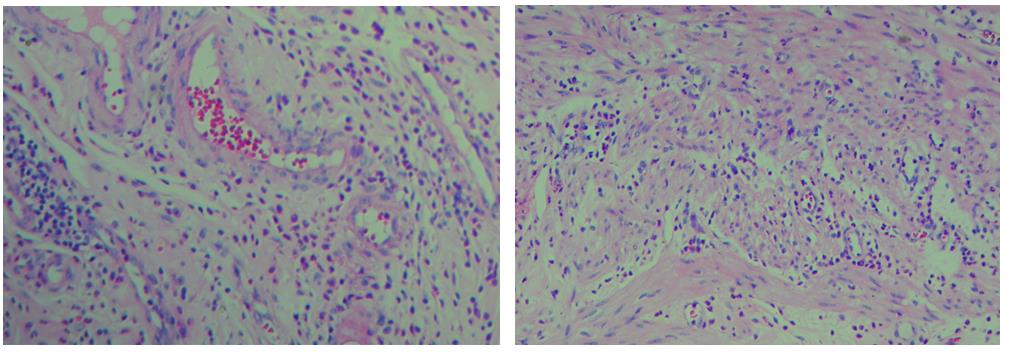

3、色彩鮮艷,核漿紅藍(lán)對比鮮明,染色效果持久穩(wěn)定,胞核結(jié)構(gòu)清晰

細(xì)胞中的細(xì)胞核由帶負(fù)電荷的酸性物質(zhì)組成,與帶正電荷的堿性染料蘇木素的氧化物三氧化蘇木紅有較強的親和力;而細(xì)胞漿則相反,因含有帶正電荷的堿性物質(zhì)而與帶負(fù)電的酸性染料曙紅Y的親和力較強;細(xì)胞或組織切片經(jīng)HE染色后,細(xì)胞核被染成藍(lán)紫色,細(xì)胞漿、紅細(xì)胞、肌纖維、膠原纖維、結(jié)締組織、嗜伊紅顆粒等被染成不同程度的紅色、粉紅色或橙紅色,與藍(lán)色的細(xì)胞核形成鮮明的對比,因此更易于觀察細(xì)胞或組織中正常成份和病變成份的一般形態(tài)結(jié)構(gòu)。

【實際染色效果】